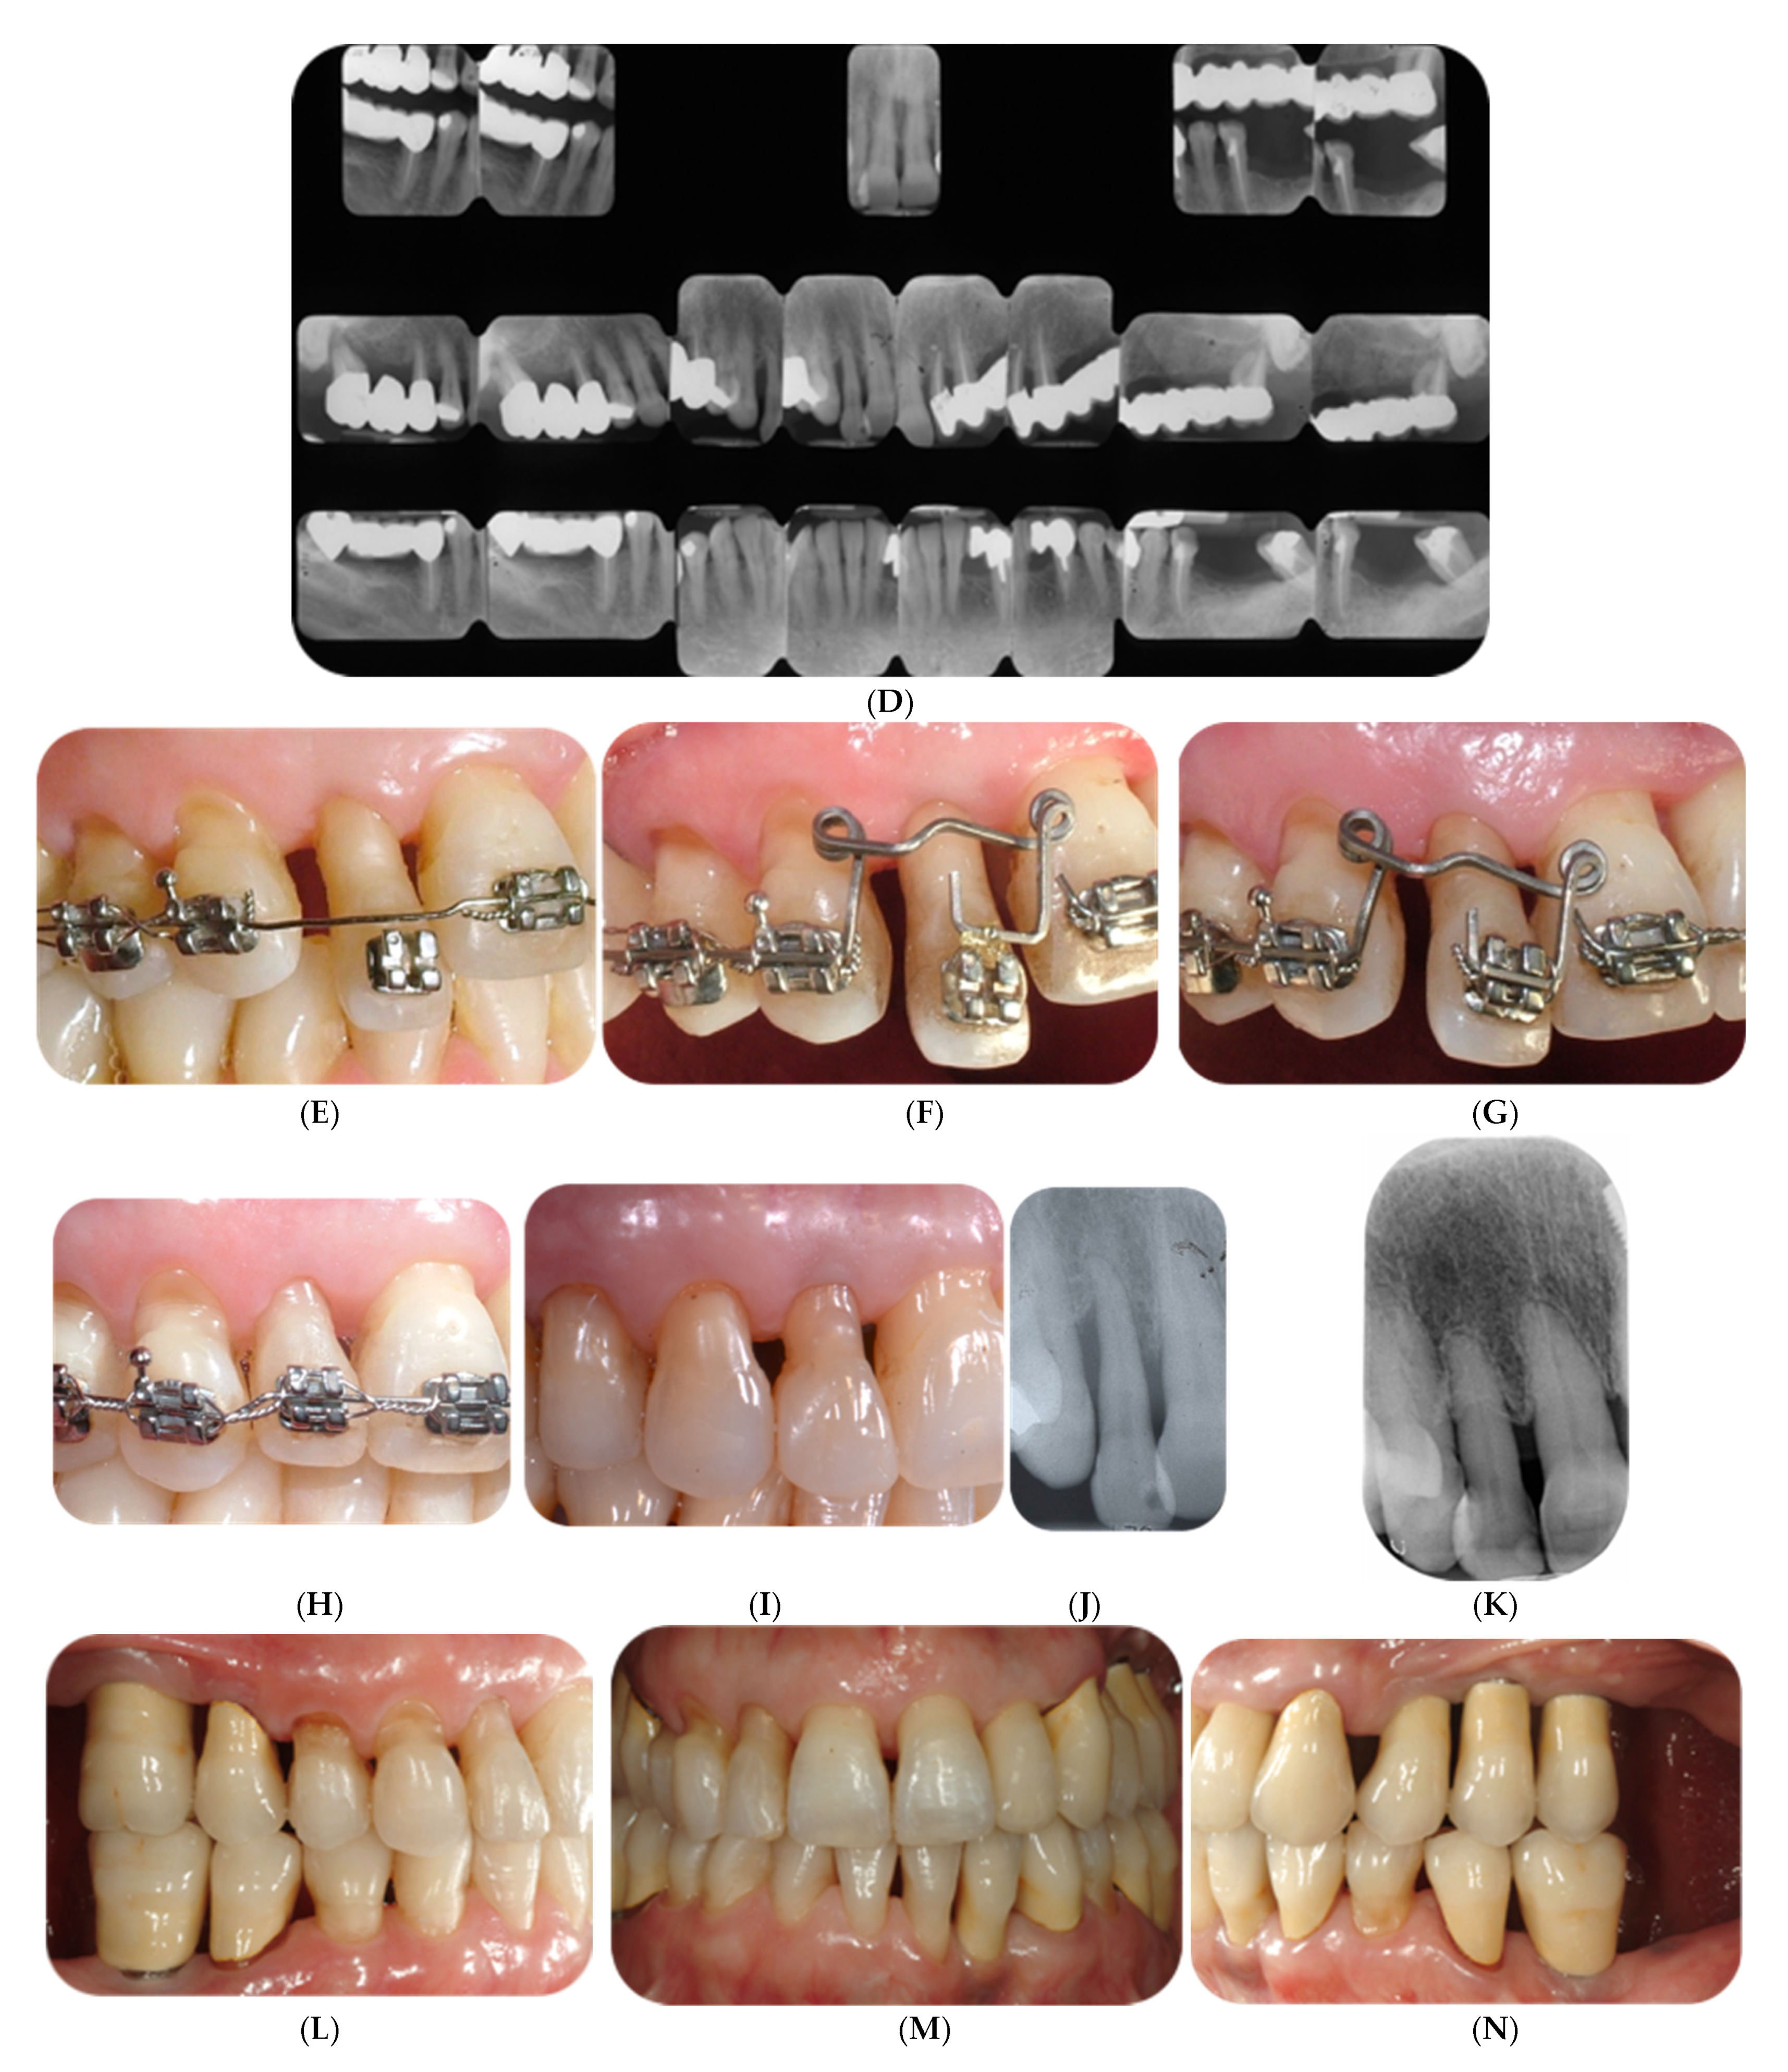

3.2. Orthodontic and Aesthetic Treatment Outcomes

3.3. Periodontal Clinical and Radiographic Outcomes